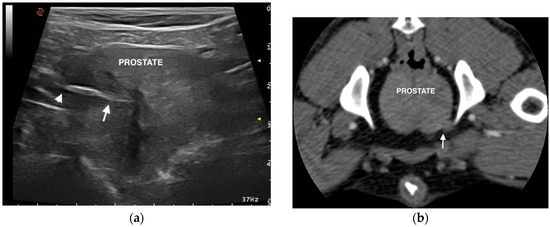

Prostatic Localization of a Migrating Grass Awn Foreign Body in a Dog

2. Case Presentation